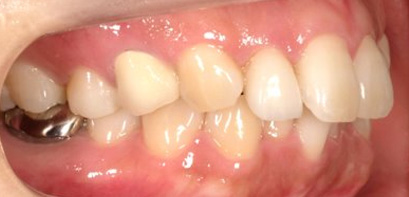

上顎前突といわれ、上顎の前歯が唇側に出ている状態を言います。

前歯が出ることで見た目の問題もありますが、口を閉じることができない、口呼吸をしてしまう、外傷などのリスクがあります。

日本人に叢生の次に多い不正咬合と言われており、自然に治ることはありません。また上の前歯が出ている事だけが気になるかもしれませんが、多くの場合、上顎の奥歯の位置に問題があることが多く、部分矯正でなく根本的な治療をした方がいい場合が殆どです。

口を閉じることができないことで、鼻呼吸でなく口呼吸をしてしまい、結果、成長期の場合顎の骨の成長を邪魔してしまうとも言われております。その他、口呼吸はアトピーなどを含むアレルギー症状の悪化、風邪を含むウイルス性の感染症にかかりやすいなどのリスクも増大してしまいます。

歯並びだけでなく全身への影響も多い為、早期の治療をおすすめ致します。